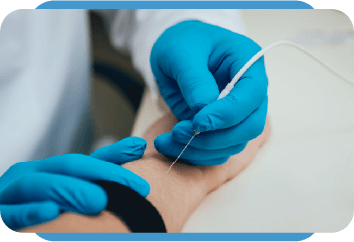

Tecnologia avançada para um diagnóstico mais preciso